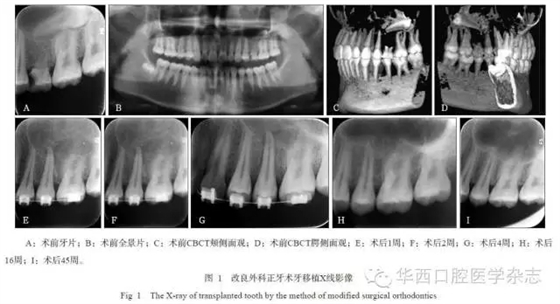

牙移植術(shù)后,均采用正畸片段弓或正畸弓絲黏接固定4~6周,術(shù)后定期隨訪6個月以上,觀察移植牙愈合狀況及X線影像改變。在術(shù)后2~12周,根據(jù)牙周愈合狀況、牙冠色澤的變化、電活力測試與X線根尖區(qū)影像等綜合評估,酌情判斷是否進行根管治療。

45例移植牙經(jīng)過手術(shù)異位移植、正畸固定4~6周后,逐漸獲得穩(wěn)固,并行使咀嚼功能。經(jīng)0.5~2年的隨訪觀察,34例移植牙均未出現(xiàn)牙根吸收、牙齒松動等并發(fā)癥,達到成功標準;11例移植牙中存在松動小于Ⅱ度、移植牙類牙周膜影增寬、牙槽骨楔形吸收、牙根吸收(但小于等于2.0?mm)等一項或幾項情況,能承擔(dān)部分咀嚼功能,達到有效標準。隨訪期內(nèi)未見失敗拔牙病例。

2組移植牙術(shù)后6個月的臨床和影像結(jié)果見表1和2。統(tǒng)計分析表明:1)A、B組的松動度、根管治療比率有統(tǒng)計學(xué)差異(P=0.021, P=0.025),而牙冠色澤變化、電活力測定無統(tǒng)計學(xué)差異(P=0.225, P>0.05)。2)A、B組的移植牙根吸收、牙槽骨吸收有統(tǒng)計學(xué)差異(P=0.025,P=0.038),而牙周膜影像改變無統(tǒng)計學(xué)差異(P=0.169)(表2)。A組療效優(yōu)于B組。